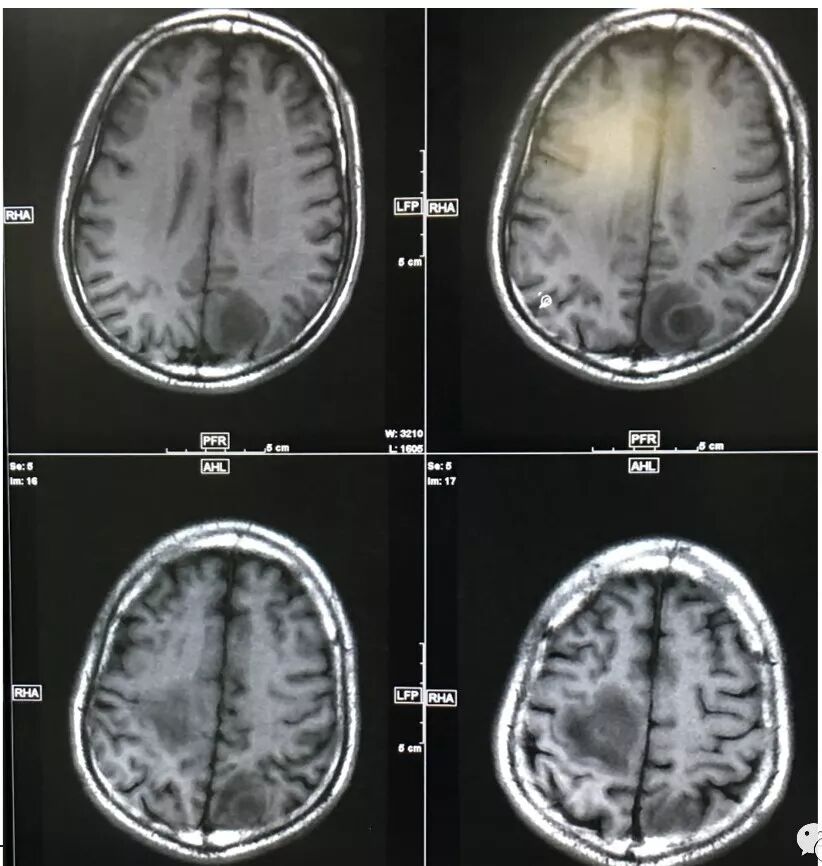

右肺下叶团块状密度增高影,边缘模糊,其内见液性低密度影,多发小气泡影及充气支气管征,考虑肺脓肿。颅内双侧顶叶长T2长T2病灶,周围水肿,DWI高信号,增强扫描囊壁环形强化,囊壁钙化,周围水肿,考虑脑脓肿。患者长期接触垃圾,什么菌都有,肺、脑脓肿,考虑肺克。再有肝脓肿就更支持了。

右肺下叶背段实变,广基底,糊墙,长轴与平行胸膜,周围有晕,支气管进入堵塞,可见低密度坏死及小空泡。颅内多发环形强化灶,符合脑脓肿三层结构,结合临床,考虑:感染性病变,隐球菌?鉴别肺克。

右肺下叶见不规则软组织影,边缘不清,内夹杂气体,背段支气管未见明显阻断,增强扫描下叶病灶内见类圆形低强化区,其边缘光滑,见低强化区壁,颅脑左侧枕叶及双侧顶叶见多发长T1长T2信号,T2高信号内见类圆形异常信号,壁呈低信号,DWI环形壁未弥散受限,内容物弥散受限,周围为水肿区,增强扫描呈多发环形强化,考虑血源型感染,颅内及右肺下叶脓肿形成

1.中年男性,以头痛等神经系统症状入院,有单侧肢体乏力,起病突然,但没有发热及呼吸系统症状,否认糖尿病病史,没有证据表明为某些特殊菌群的易感人群。

2.影像右肺下叶大片高密度影,整体边界模糊柔和,中央见圆形液化区及微小气泡影,内壁相当光整,环形强化,未见明确壁结节。双肺门及纵隔未见增大淋巴结。这样的病灶更符合细菌性肺脓肿,以肺炎克雷伯杆菌感染最为常见。

3.脑内多发混杂信号病灶,显著长T1、显著长T2信号为主。注意TW1及TW2均显示环形等密度影(这在转移瘤是非常罕见的)且出现相应的环形强化。中央液化区DW扩散受限以及周边广泛水肿等,都符合典型多发脑脓肿改变。

综上患者符合肺脓肿及脑脓肿诊断,病原菌以肺炎克雷伯杆菌等感染可能性较大